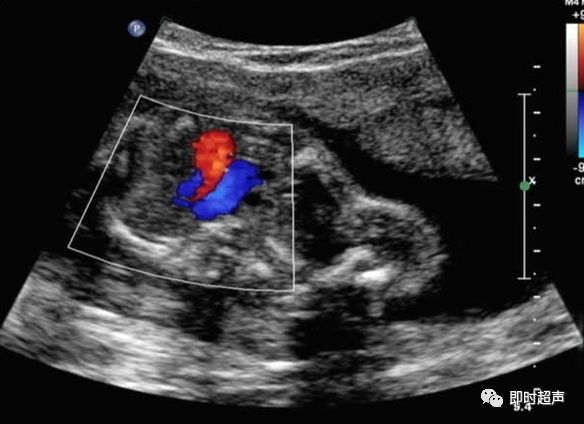

五、血流方向的异常

主动脉弓或肺动脉血流方向相反是导管依赖型心脏畸形的典型表现

主动脉弓血流反向

左心发育不良综合症(二尖瓣或主动脉瓣闭锁或重度狭窄)

肺动脉血流反向

右心发育不良综合症(三尖瓣或肺动脉瓣闭锁或重度狭窄)